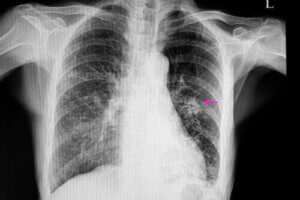

إذا كان السرطان هو المسبب، تتسم العقيدات بمظهر غير منتظم ذي حواف غير محددة بشكل واضح، وهو ما يمكن التأكد منه عن طريق الأشعة السينية. بالإضافة إلى ذلك، تميل العقيدات المسرطنة إلى أن تكون أصغر حجمًا من العقيدات الحميدة.

بعد ذلك، يحتاج الطبيب إلى عمل بعض الأشعة لتحديد مكان العقيدات. بالإضافة إلى ذلك، ستساعده الصور على تحديد بعض الخصائص كالشكل والحجم.

التعرف على هذه الخصائص من الأمور المهمة لاكتشاف ما إذا كانت العقيدات حميدة أم مسرطنة.

أكثر الوسائل التشخيصية استخدامًا في هذه الحالات هي الأشعة السينية على الصدر والتصوير المقطعي المحوسب.